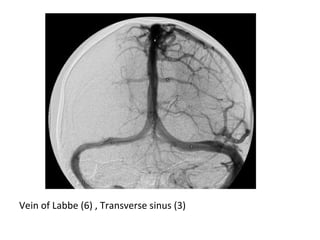

Vein of Labbe (6) , Transverse sinus (3)